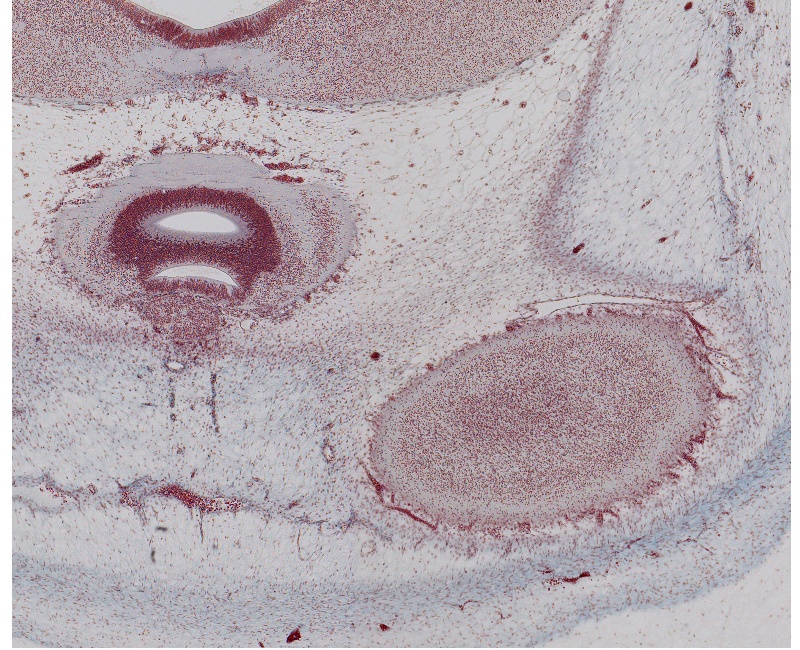

Tissue

–

Epiphysis, Pineal Recess, and Edge of Cerebral Hemisphere

Carnegie Embryo #9226

14-01-01